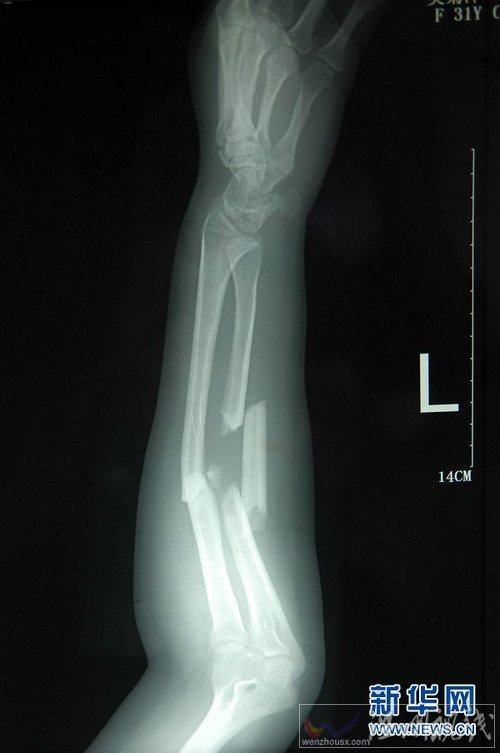

杭州英雄妈妈吴菊萍徒手接住坠楼女童 吴菊萍受伤手臂X光片

这是7月3日拍摄的吴菊萍受伤左臂的X光片,医生诊断为手臂左尺桡骨多段粉碎性骨折。 7月2日下午1点半左右,浙江杭州滨江区的一处住宅小区内,一名2岁女童从10楼突然坠落,在楼下的吴菊萍奋不顾身地冲过去用双手接住孩子。目前,被接住的女童正在浙江省儿童医院抢救,而徒手接住小女孩的吴菊萍,左手臂尺桡骨多段粉碎性骨折,正在富阳市中医骨伤医院进行消肿处理,等待手术治疗。今年31岁的吴菊萍,已有一个7个月大的儿子,一家人与坠楼女童一家同住一个小区内,事发之前素未谋面。新华社记者 黄宗治 摄